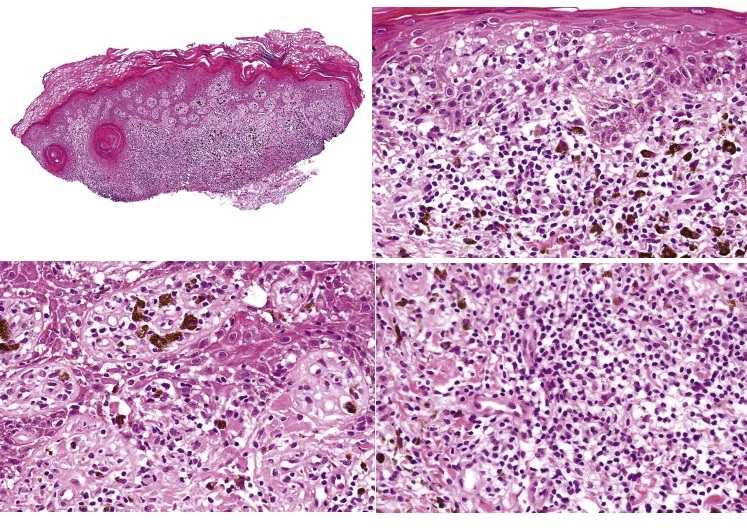

Lichen striatus. Obliquely cut section. There is marked hyperkeratosis with parakeratosis, acanthosis, inflammation, and pigment incontinence

Lichen striatus. This field highlights the massive pigment incontinence.

Lichen striatus. There is a dense dermal lymphohistiocytic infiltrate